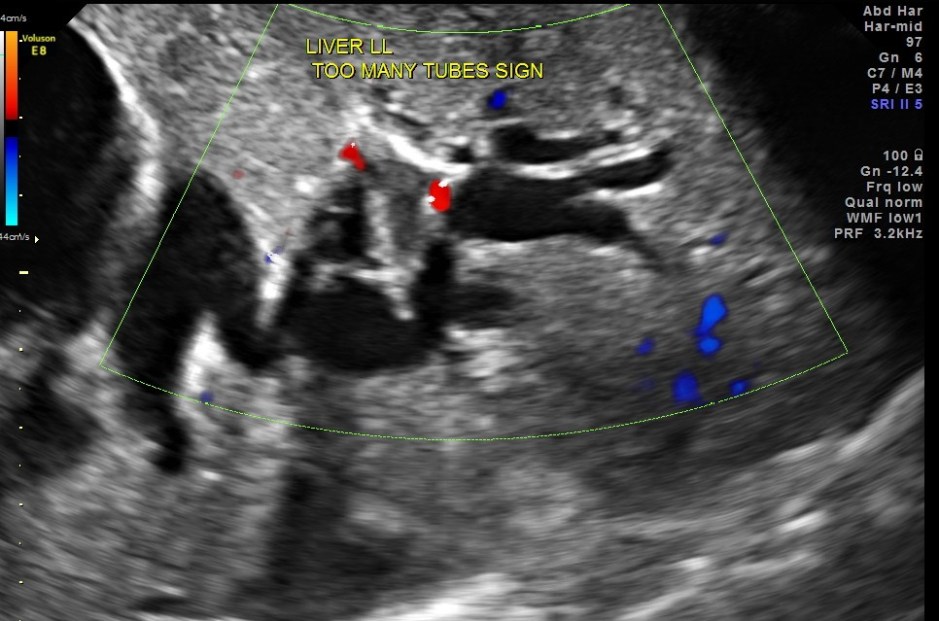

Courvoisier’s law (or Courvoisier syndrome, or Courvoisier’s sign or Courvoisier-Terrier’s sign) states that in the presence of an enlarged gallbladder which is nontender and accompanied with mild jaundice, the cause is unlikely to be gallstones. Usually, the term is used to describe the physical examination finding of the right-upper quadrant of the abdomen. This sign implicated possible malignancy of the gall bladder or pancreas and the swelling is unlikely due to gallstones.

This was a 55 year old man with history of jaundice and upper abdominal pain .